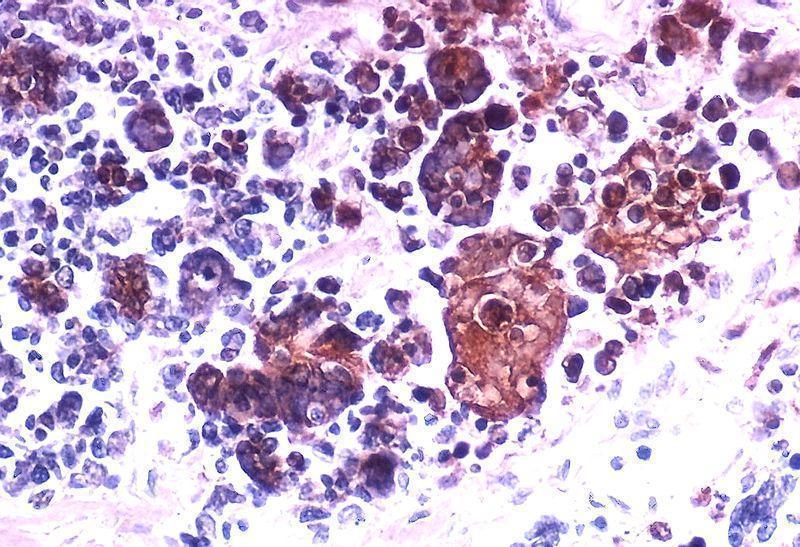

When viruses enters tumour cells, they replicate in an unchecked manner, resulting in the bursting of the tumor cells. The principle of using a virus to target cancer is that tumours usually have weak immune defenses targeted at pathogens such as viruses because tumours release less interferon. For cancer-killing virus therapy to be successful, the virus must not be easily recognized by the immune system to allow it to replicate effectively in the tumour host.

With recent technologies, developing oncolytic (cancer-specific) viruses that target multiple tumours is the next big step in this field of research. Very few of these viruses are currently on the market however. One of these viruses is a modified version of herpes simplex virus (HSV)-type 1 which has been approved for melanoma cases. The virus is tumour specific because of an ICP34.5 gene knock-out. Removing this gene decreases the ability of the virus to replicate in non-cancerous cells. However, this virus can only be administered by injection which causes a problem for metastatic cancer where one may not know all the sites affected by the cancer. Another disadvantage of HSV is that it may be easily eliminated by the immune system as most people have a memory response towards it due to prior infection.